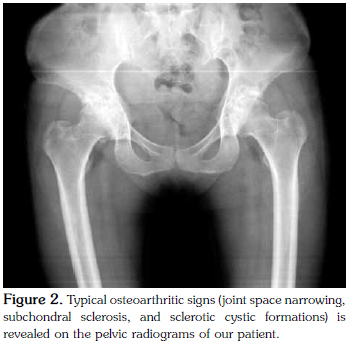

A 44-year-old female patient was admitted to our clinic with complaints of episodic pain, swelling attacks, and progressive deformity in both wrists and metacarpophalangeal joints lasting for five years. Based on her complaints, she had been diagnosed with rheumatoid arthritis and taken methotrexate, sulphasalazine, and prednisolone for two years, however, the patient had discontinued her treatment a year earlier due to ongoing symptoms. Physical examination revealed limited range of motion of both wrists and flexion deformity of the fingers without active inflammation signs. Hand X-ray showed typical signs of osteoarthritis characterized by narrowed joint spaces, subchondral sclerosis, and cyst formation. The distal and proximal interphalangeal joints were markedly preserved, and there were large, hook-like osteophytes in the heads of the metacarpal bones, indicating a typical presentation of hemochromatosis. Laboratory tests revealed that the erythrocyte sedimentation rate and C-reactive protein and uric acid levels were within the normal range, and the antibody tests were negative for rheumatoid factor, anti-nuclear antibodies, and anti-cyclic citrullinated peptides. Although the serum iron and ferritin levels were normal, there was a high transferrin saturation rate. Magnetic resonance imaging demonstrated a hepatic iron concentration of 44 μmol/g (reference: <36 μmol/g). Genetic studies showed homozygous for the H63D mutation. Based on these findings, the patient was diagnosed with hereditary hemochromatosis and scheduled for follow-up visits. In conclusion, hemochromatosis should be considered in the differential diagnosis in patients suffering from slow-progressing arthritis with chronic deformity.

A physical examination revealed decreased ROM in both wrists and the MCP joints with accompanying flexion deformities; however, the affected joints did not demonstrate any signs of active inflammation. Furthermore, the patient's hip joint movements were painful and restricted. Typical signs of osteoarthritis (OA) (irregular narrowing of joint spaces, subchondral sclerosis, and sclerotic cyst formation) were seen on hand radiograms (Figure 1). Strikingly, the distal interphalangeal (DIP) and PIP joints were intact, and hook-like osteophytic formations on the heads of the metacarpal bones were seen, which is typical of hemochromatosis. Pelvic radiograms revealed irregular joint space narrowing, sclerotic changes, and subchondral cysts involving the hip joints (Figure 2). Additionally, the laboratory findings showed a normal erythrocyte sedimentation rate (ESR) and C-reactive protein (CRP) levels, and the patient tested negative for rheumatoid factor (RF) as well as anti-cyclic citrullinated peptide (anti-CCP) and antinuclear antibodies (ANA). Furthermore, the serum uric acid level was normal, and the liver function test results were within normal limits. Although the serum iron and ferritin levels were also within normal limits, the transferrin saturation rate was higher (69.71%) than normal (<55%). Moreover, the patient's estimated hepatic iron concentration was 44±20 μmol/g (normal <36 μmol/g) using T2 sequences in abdominal magnetic resonance imaging (MRI). A genetic examination also determined the existence of a homozygous H63D mutation; therefore, the patient was diagnosed with HH based on the clinical, radiological, and laboratory findings.